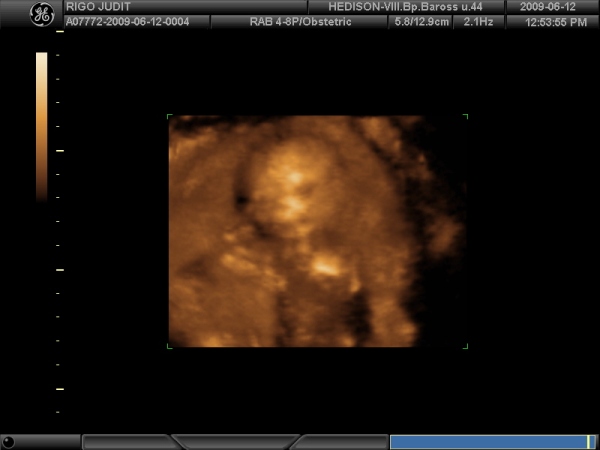

Ime Miss Bogyó:

Kép

4,5 mm és a Szívecskéje 140-et ver, imádom!!!!!!!!!!!!!!!!